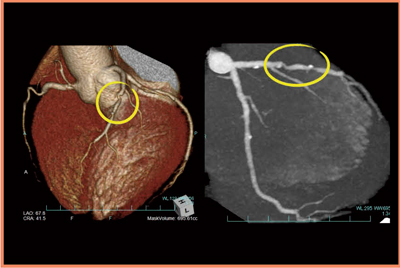

・症例3:60歳代,男性。LADにステント留置の既往があり,フォロー中に非特異的な胸痛を訴えた。

不整脈があるため,100kV,R-R 30〜80%とし,念のために2beat scanして,得られたデータから最適な画像を取得することとした。LADの近位部から中間部にかけ,ステントとともに強い石灰化が描出されたものの,高速スキャンと安定した画像のcurved MPRで,ステント内腔には有意狭窄がないことを確認できた(図4)。実効線量は7.3mSvだが,64列CTによるヘリカルスキャンと比較すると,かなり少ない被ばく線量で確実に検査を行うことができた。

図4 症例3:curved MPR像によるステント内腔の評価